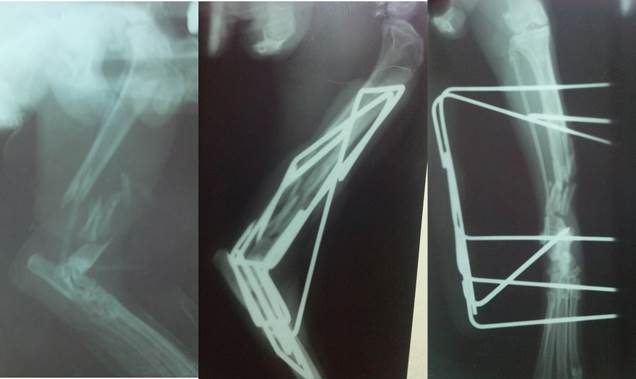

En el posoperatorio se guio la cicatrización, se manejó el dolor y se indicó una combinación de antibióticos para prevenir sepsis posquirúrgicas. Entre los fármacos usados estuvieron Meloxican (0,1 mg/kg cada 24 h por cinco días), Dipirona (28 mg/kg cada 12 h durante siete días) para manejar el dolor. Se utilizó Ceftiofur (3 mg/kg cada 24 h en la primera semana), Metronidazol (15 mg/kg cada 12 h por siete días) y Enrrofloxacina de larga acción (5 mg/kg cada 72 h, dos dosis). Se indicaron consultas periódicas cada una semana para valorar la evolución del felino y estudios radiológicos posoperatorios inmediatos, a las 3, 8 y 10 semanas. Por escasa disponibilidad de centros donde se realicen estudios imagenológicos veterinarios, solo se pudo realizar un Rx a las cinco semanas (Fig. 8).

Fig. 8.

Imágenes radiológicas de izquierda a derecha, vista latero lateral (LL) antes de la cirugía, LL y cráneo-caudal a las cinco semanas. / Radiological images from left to right, lateral view (LV) before surgery, LV and craniocaudal at five weeks.

Las Figuras 7 y 8 muestran la evolución favorable del caso a las cuatro y cinco semanas del postoperatorio. En la Figura 7 se puede observar la marcha del animal, no presentaba claudicación ni dolor del miembro afectado; solamente una marcha en ocasiones torpe por las molestias que generaba la banda estabilizadora de acrílico en la porción medial que rosaba con la región inguinal.

El estudio radiológico en la vista latero-lateral de las cinco semanas mostró la alineación casi perfecta de los fragmentos distales desplazados cranealmente; en el Rx cráneo-caudal se observa una pequeña desviación (sin desagrupamiento de fragmentos) que biomecánicamente no influye de manera negativa sobre la consolidación ósea (10) y la futura marcha del paciente, de manera que el pronóstico fue favorable.

El inicio de la formación de callo óseo (Fig. 8) a las cinco semanas permitió que en la semana 10 posquirúrgica se retirara el tutor externo sin dificultad alguna sobre la extremidad, específicamente en la articulación.